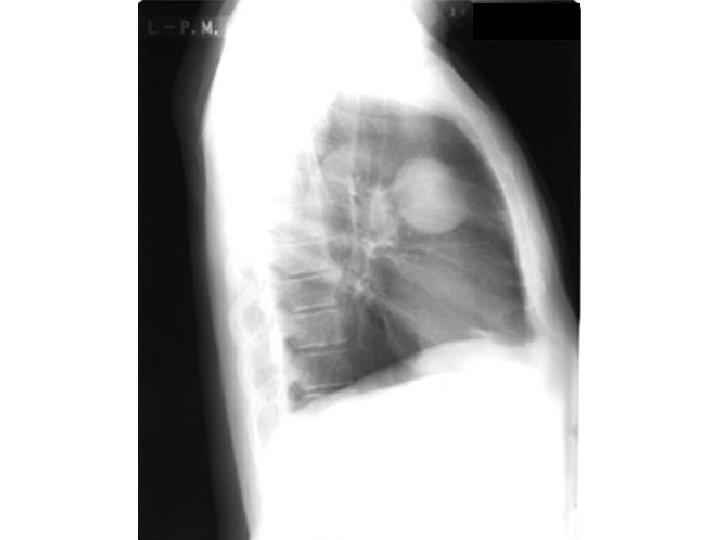

Mass

Homogenous Sharp margin No respect Mass